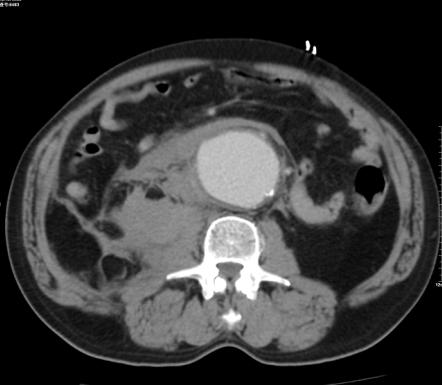

增强后:腹主动脉下段至左右髂总动脉上端明显扩张,最宽处约6.8cm,上下径约为13cm,成瘤样改变,边界清楚,形态规整。

1.腹主动脉瘤。(腹主动脉下段至左右髂总动脉上端)

3.右肾周及腹主动脉周围,中上腹腔见条带状及片状稍低密度影(多考虑腹腔包裹性积液,请结合临床病史。